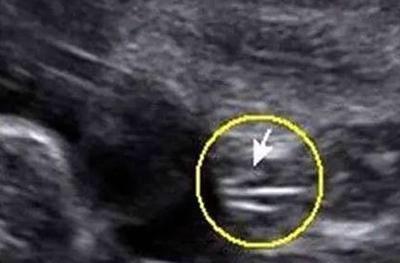

3.如果B超单子有出现肾孟扩张90%或者分离,十有八九就是男宝宝了。当胎儿憋尿时,就会发生肾盂分离,因为在一个医学杂志里说过,90%的肾盂分离发生在男宝身上,通常出生的时候都会拉泡尿解决这个问题。因此如果你的B超单子上有肾盂分离,说明男宝的概率远远大于女宝。

男宝不一定会肾盂分离,肾盂分离很大可能就是男宝,方法很简单,赶紧拿起B超单子看看吧。希望各位准妈妈都能得偿所愿。